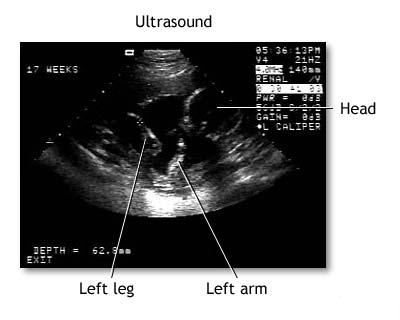

Ecografia fetala